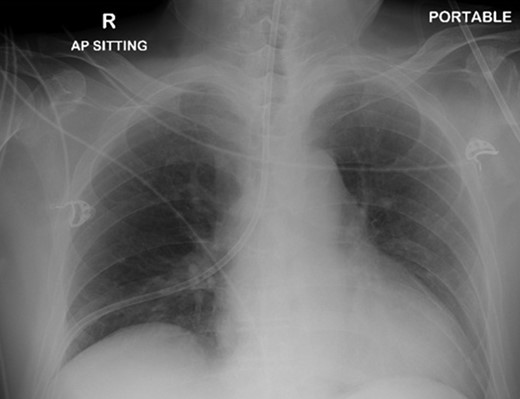

A 72-year-old male was admitted to a tertiary hospital following a cerebrovascular accident. His neurological deficits were global aphasia, dysphagia and right hemiplegia. He underwent a routine NGT change with a small bore NGT by an experienced nurse on Day 2 of admission. The nurse was unable to obtain any aspiration from the newly inserted NGT and a chest radiograph was done to confirm placement as per hospital protocol. This showed a malpositioned NGT, traversing the right main bronchus with the tip of tube in the right costophrenic sulcus (Fig. 1). She was alerted about the chest radiograph findings and removed the tube before reinserting another NGT. The subsequent aspiration from the NGT had a pH of 7, hence another chest radiograph was done which now demonstrated a right pneumothorax (Fig. 2). The pneumothorax was likely due to intrapulmonary placement of the earlier NGT.

Chest x-ray showing the nasogastric tube, traversing the right main bronchus with the tip in the right costophrenic sulcus.

Chest X-ray following removal of the nasogastric tube, with interval development of a right sided pneumothorax.